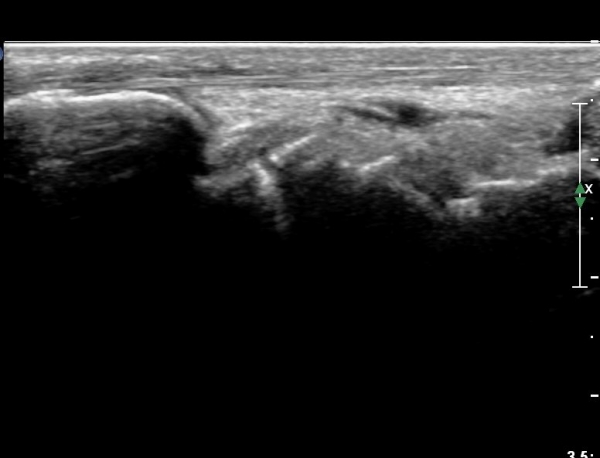

¼Õ¸ñ ¿ä°ñÃø ÁÖ»ó°ñ Á¾´Ü¸é °Ë»ç¿¡¼ ÁÖ»ó°ñ ÇÇÁú°ñ ¿¬¼Ó¼º ¼Ò½ÇÀÌ ¶Ñ·ÈÇÏ°í µ¿¹ÝµÈ ¿¬ºÎÁ¶Á÷ ºÎÁ¾ÀÌ °üÂûµÊ(»çÁø 3, 4)/

È®ÁøÀ» À§ÇÑ ÃÊÀ½ÆÄ°Ë»ç¿¡¼ ÁÖ»ó°ñ °ñÀý È®ÀÓ µÊ.